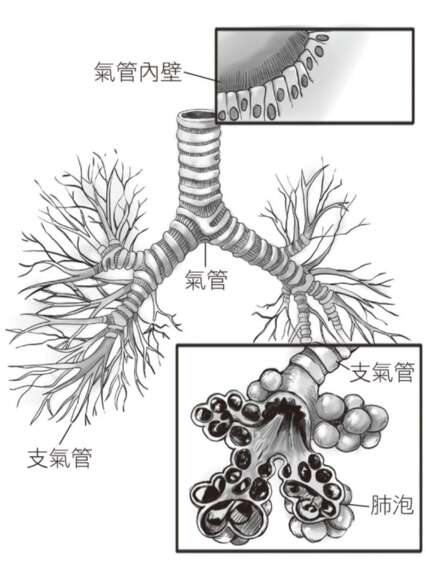

腦其實含有一個透明的液體叫腦脊髓液,就像右頁這張圖淺藍和深藍的區域所示,環繞著腦和脊髓的組織。過去,我們會以為這個液體最多隻是做為保護腦和脊椎的緩衝,就像用水溫柔地捧住腦,免得這麼柔軟的組織在頭骨裡摔壞了。沒想到,等我們睡著了,這個液體還會大量進入腦的組織,就好像在整體地沖洗白天頭腦運作累積下來的廢物。

最重要的是,腦部的這個清理系統在睡眠時,清理效率比醒著時高出60%3。腦部的清理程序,大部份都是在夜裡睡眠時發生。這個過程會讓腦細胞和細胞之間的液體量加倍,並且帶到腦內的深處,等於在腦中造出了一套臨時的運河系統。就像威尼斯的運河,把小城的每個角落都連起來。不同的是,威尼斯運河是人造的系統,而腦內是天然的系統。我們清醒的時候,腦細胞之間液體的流動是受限的,是等我們睡著後才開始流動,從腦部移除代謝的廢物。沖洗後,還會將廢物堆積到靜脈週邊,透過頸部的淋巴把它帶走。